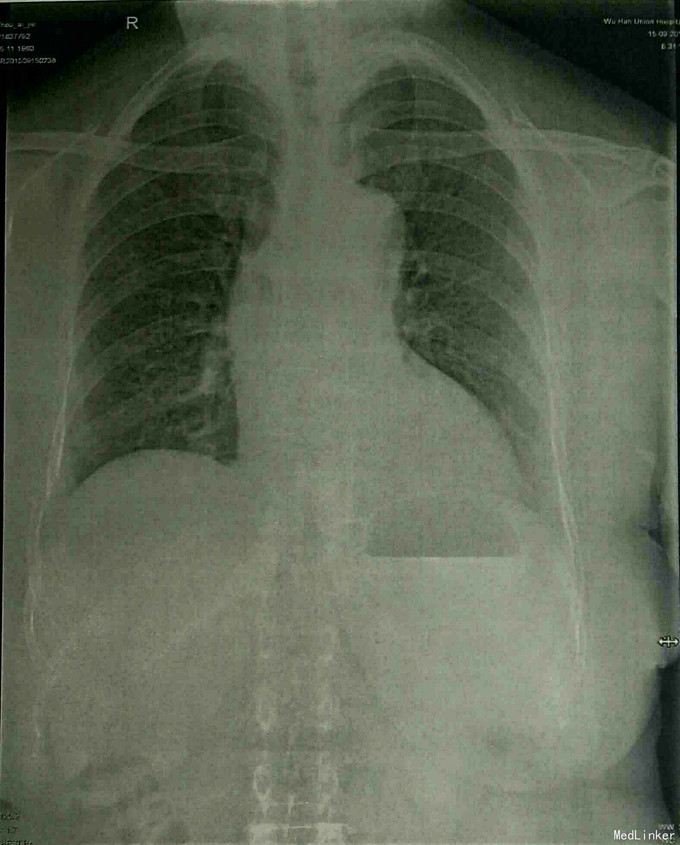

查体:T:36.5℃,P:82次/分,R:20次/分,BP:122/73mmHg。神志清楚,查体合作,面容正常,全身浅表淋巴结无肿大。心率82次/分,律齐,心音正常,各瓣膜区未闻及杂音。肺部心间波动正常,压痛及反跳痛阴性,无异常隆起及凹陷。双肺呼吸音清,未闻及干湿罗音及胸膜摩擦音。腹部外形正常,全腹柔软,未及包块,肝脾肋下未触及。双下肢无水肿。生理反射存在,病理反射未引出。 专科情况:右侧耳廓前下方见一手术疤痕,右侧外耳道口有一肿物堵塞,不能窥及鼓膜,外耳道口处有渗血。 辅检:门诊CT示:1、右外耳道口软组织稍显增厚,2、双侧中耳及内耳未见明显异常。术前常规检查未见异常。余见下图。